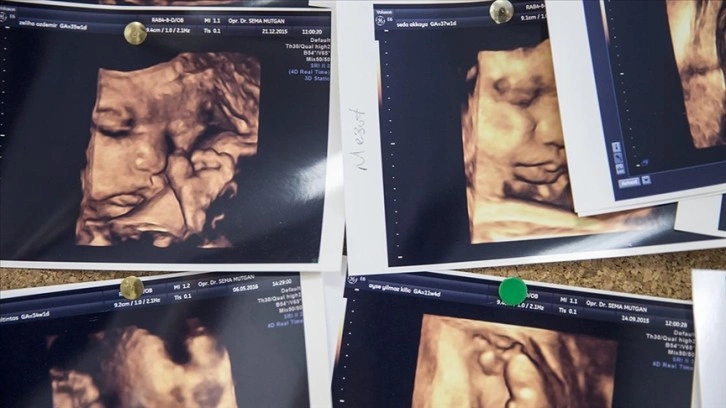

Anne karnındaki bebek sayısının iki veya daha fazla olması durumuna çoğul gebelik deniliyor.

Türkiye'de de çoğul gebelikler arttı

Türkiye İstatistik Kurumunun (TÜİK) verilerine göre, 2019'da doğumların yüzde 3,1'i çoğul doğum olurken, bu doğumların yüzde 96,4'ünün ikiz, yüzde 3,4'ünün üçüz ve yüzde 0,2'si dördüz ve daha fazla bebek oldu.

2019'da yüzde 3,1 olan çoğul doğum oranı 2020'de yüzde 2,9'a gerilerken, 2021'de tekrar yüzde 3,1'e yükseldi.

2022'deki 1 milyon 35 bin 795 doğumun yüzde 3,2'si çoğul doğum oldu.